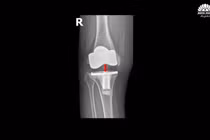

Chữa thành công biến chứng khớp gối nhân tạo hiếm gặp sau 5 năm

Thay thế khớp mới bằng kỹ thuật thay khớp gối gióng trục động học, không cắt gân cơ với đường mổ nhỏ, ít xâm lấn, giúp bệnh nhân đi lại sau 1-2 ngày.

Không thể đứng vững sau 4 năm thay khớp gối

5 năm trước, bà Oanh (63 tuổi) bị thoái hóa khớp gối độ IV nghiêm trọng, đau đớn, hạn chế vận động, ảnh hướng lớn đến cuộc sống nên bà đã quyết định phẫu thuật thay khớp gối để cải thiện vận động.